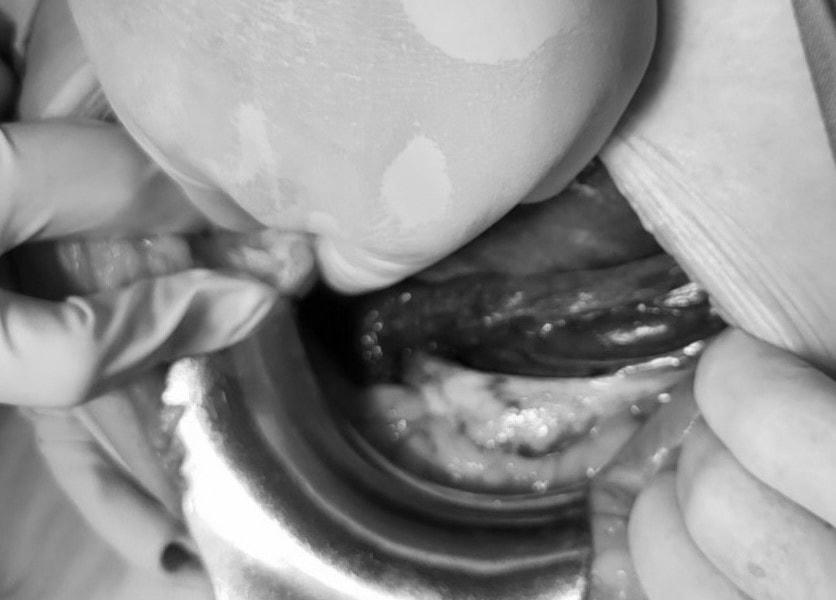

Khi phẫu thuật, rạch da theo đường trắng giữa dưới rốn qua các lớp vào trong ổ bụng, kíp phẫu thuật của Bác sĩ CKII Đàm Văn Hưng - Trưởng Phòng Kế hoạch tổng hợp nhận thấy tử cung sản phụ bị tím đen và xoắn mặt sau tử cung ra mặt trước tử cung, buồng trứng 2 bên cũng tím đen.

Kíp phẫu thuật xác định sản phụ bị xoắn tử cung - một bệnh lý vô cùng hiếm gặp khi chuyển dạ và nhanh chóng xoay tử cung về vị trí bình thường. Tiếp đó, các bác sĩ rạch ngang đoạn dưới tử cung để lấy thai và đón em bé nặng 3,2kg. Ngay sau khi được bác sĩ Sơ sinh cấp cứu thì em bé đã cất tiếng khóc chào đời trong niềm vui mừng của toàn bộ kíp trực. Sau khi lấy thai, kiểm tra thấy tử cung, buồng trứng, vòi trứng hồng trở lại, các bác sĩ quyết định khâu phục hồi và bảo tồn tử cung giúp bảo toàn khả năng sinh sản của người phụ nữ.